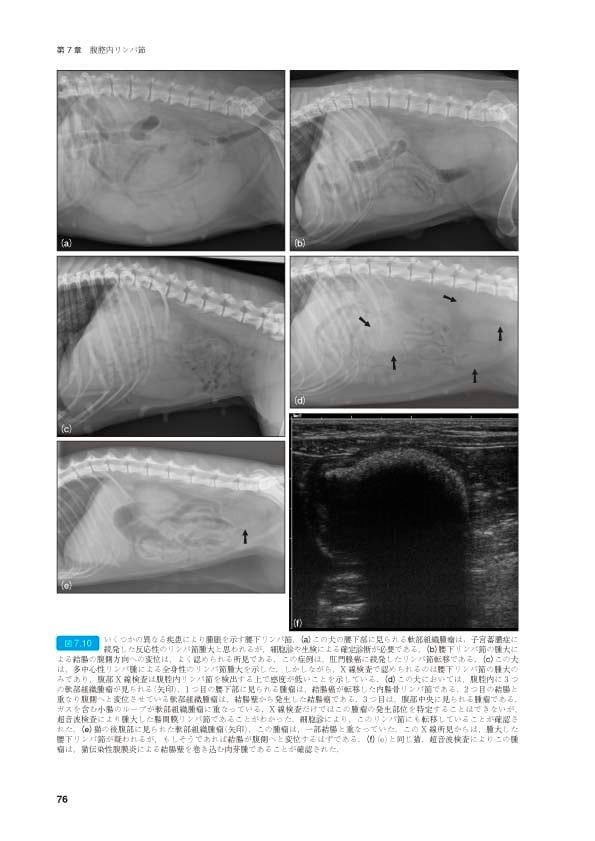

犬と猫の腹部外科に関する詳細なマニュアル。- タイトル: 犬と猫の腹部外科マニュアル- 編集者: John M. Williams and Jacqui D. Niles- シリーズ名: BSAVA マニュアルシリーズ表紙にテープ跡があります。ご覧いただきありがとうございます。| カテゴリー: | 本・雑誌・漫画>>>本>>>健康・医学 |